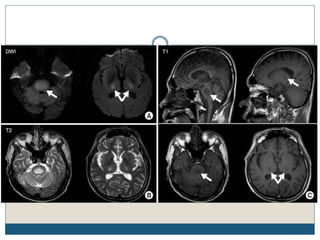

Typical MRI lesions

 Trident shaped / spreading bushfire pattern in central pons

 Signal characteristics of affected region include:

 T1: mildly or moderately hypointense

 T2: hyperintense, sparing the periphery and corticospinal tracts

 FLAIR: hyperintense

 DWI: hyperintense

 ADC: signal low or signal loss

 T1 C+ (Gd): usually there is no enhancement

 Radiologic findings do not improve over time, despite complete or nearly complete

clinical recovery

Typical MRI lesions Trident shaped / spreading bushfire pattern in central pons  Signal characteristics of affected region include:  T1: mildly or moderately hypointense  T2: hyperintense, sparing the periphery and corticospinal tracts  FLAIR: hyperintense  DWI: hyperintense  ADC: signal low or signal loss  T1 C+ (Gd): usually there is no enhancement  Radiologic findings do not improve over time, despite complete or nearly complete clinical recovery